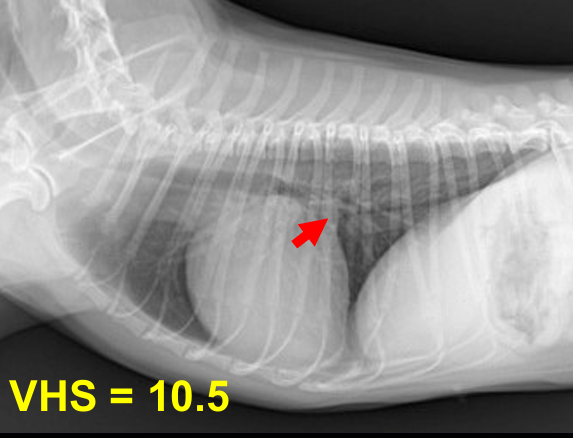

| 3기 (Severe : 좌심실까지 확실히 커짐) |

![]() |

| 1) 좌심방-좌심실 경계가 사라지고 흉벽과 가까워짐 ⇒ 우심부전까지 발생. 2) Tracheal elevation도 매우 뚜렷. 3) 좌심실, 좌심방의 피가 완전히 섞여 와류가 생김 (Aliasing) 4) 기침, syncope, 폐수종까지 발생 |